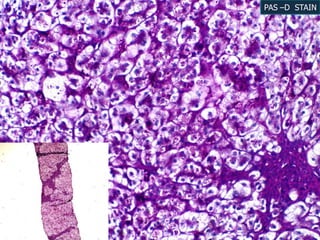

LIVER BIOPSY

B/529/13

H & E 10X

H & E 40X

H & E 20X

Reticulin stain

PAS –D STAIN

PERL’S STAIN 20X

HPE diagnosis

 Precirrhotic liver disease with periportal

hepatitis and cholestasis was opined